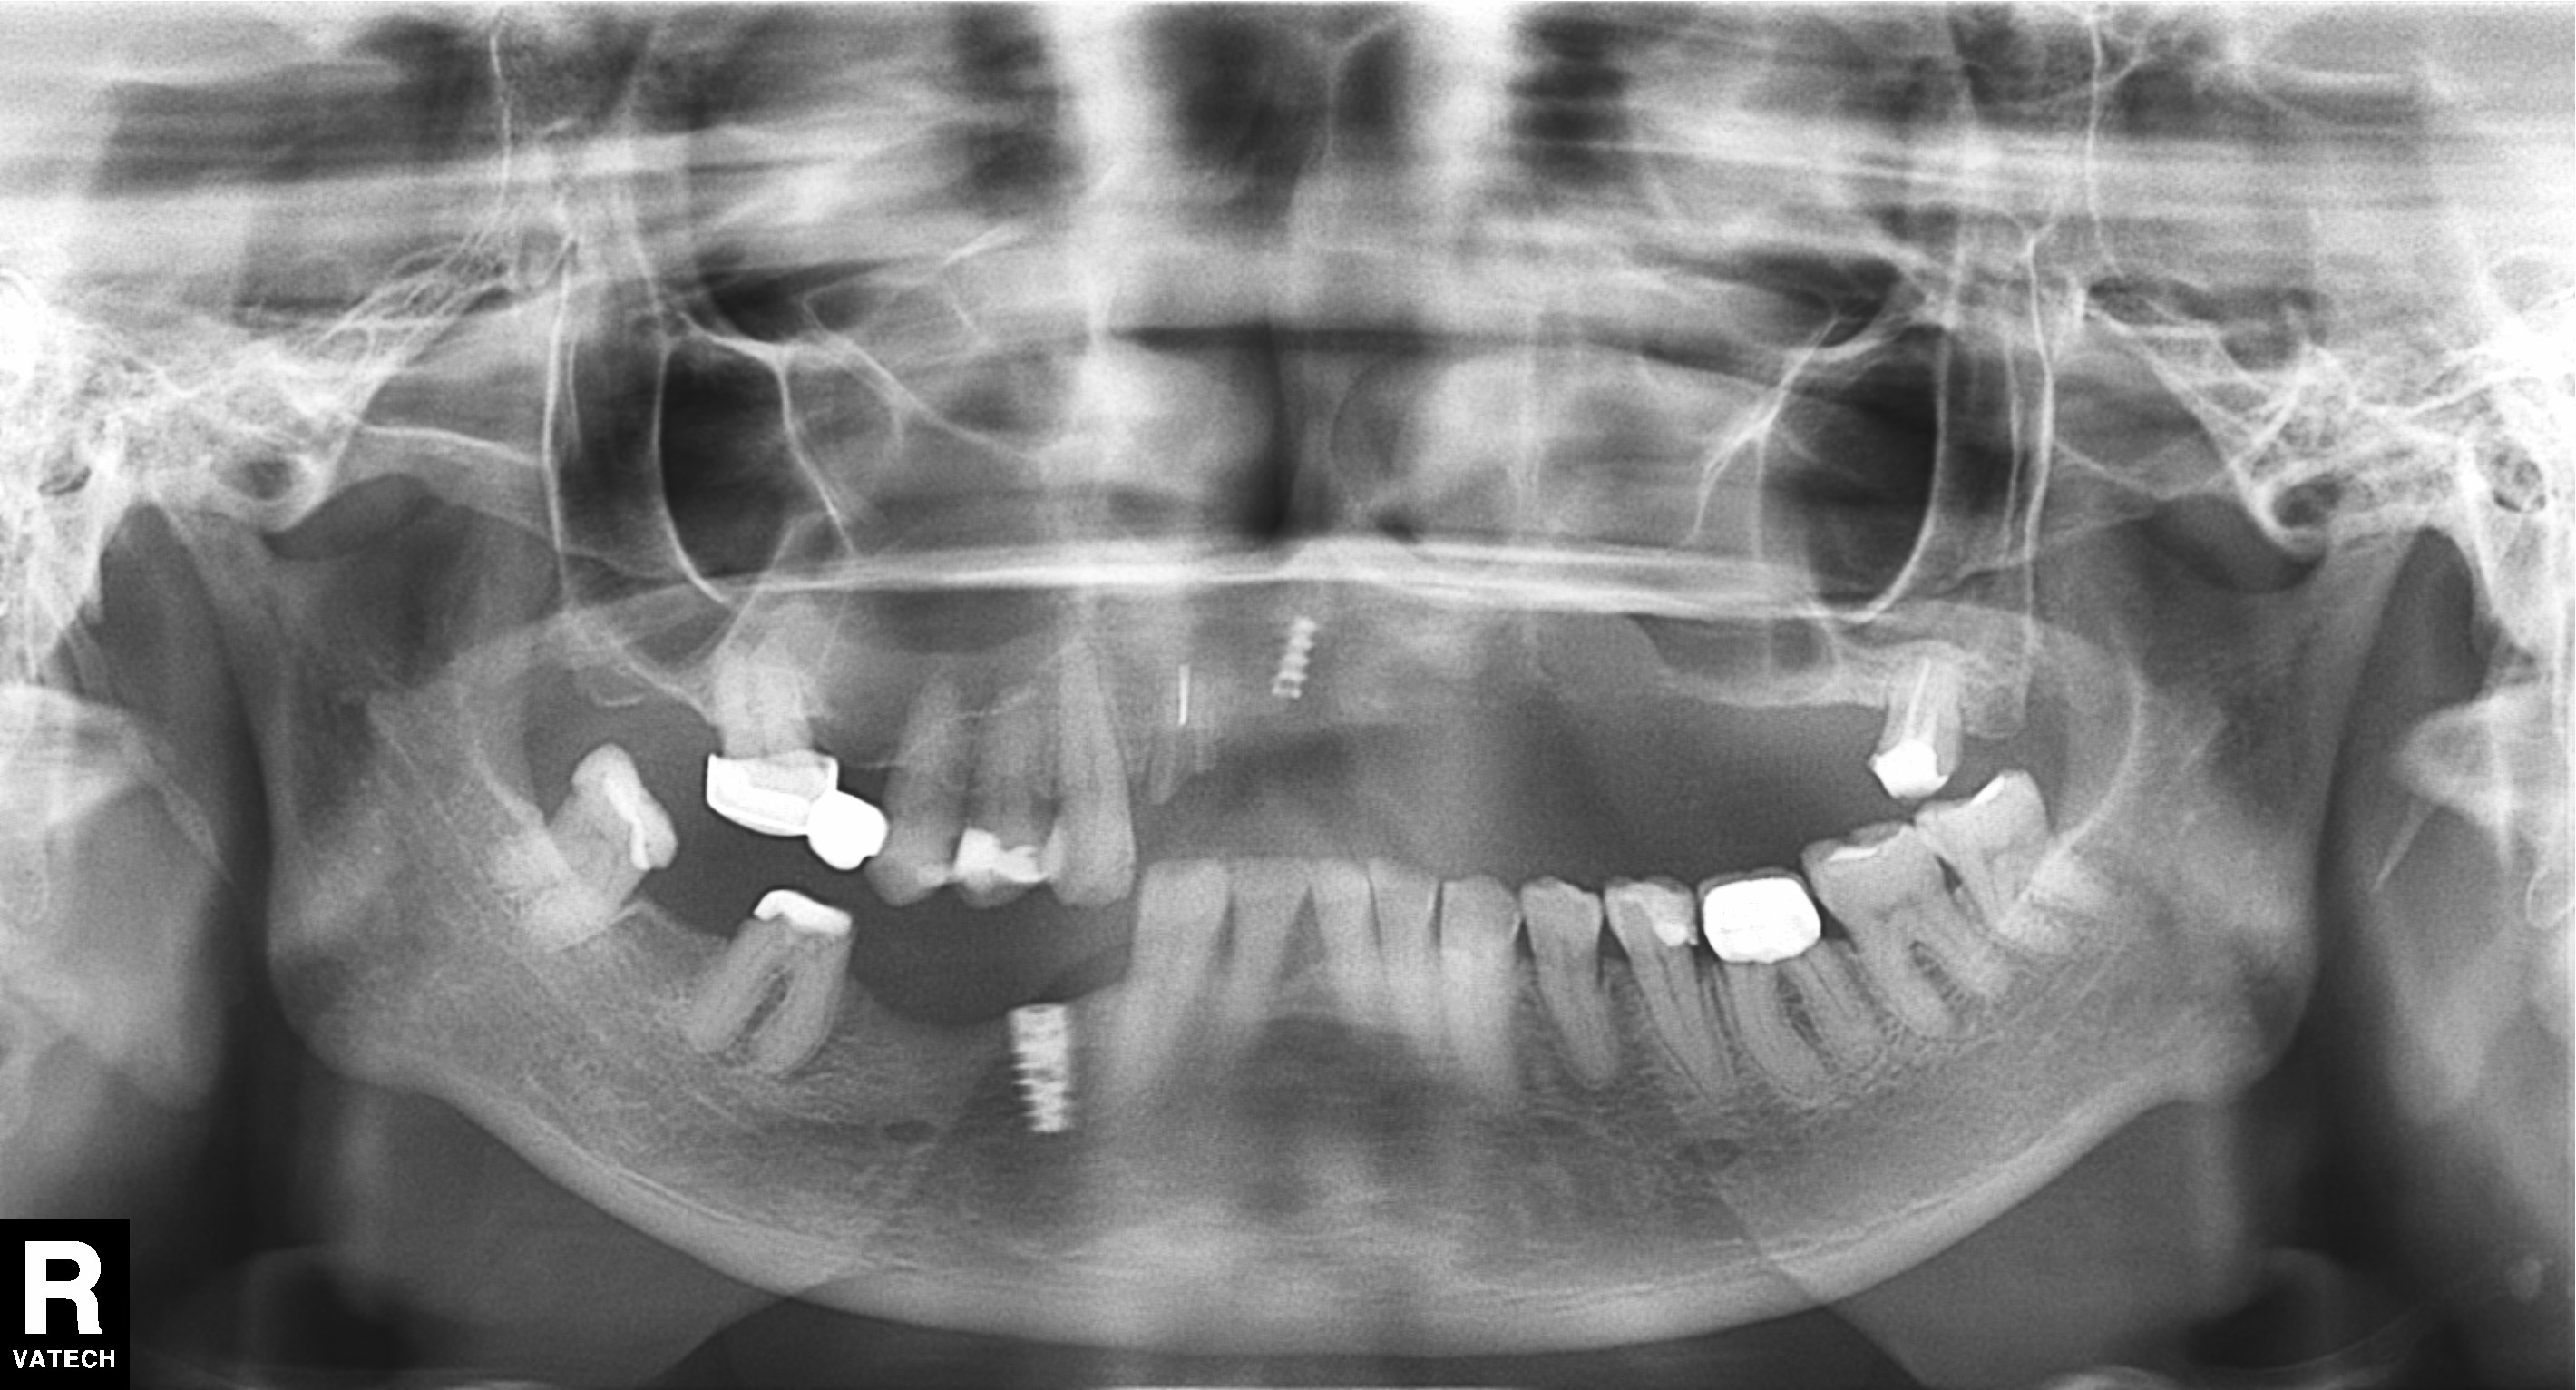

Old Detal Implant removing, Dental implant, Sinus-lifting, Bone graft

63 y.o, Kazakhstan

Operating dentist:Roh Hyun Ki